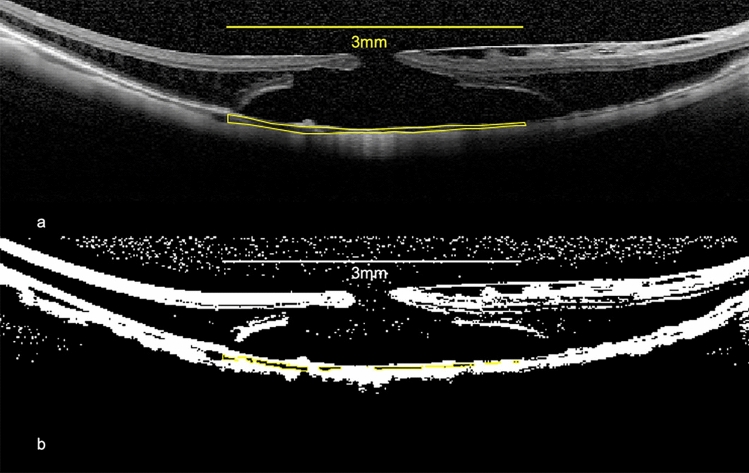

Methods: We measured the best-corrected visual acuity (BCVA), intraocular pressure (IOP), CA, LA, SA, CVI, and CT preoperatively and 1, 3, and 6 months postoperatively in 10 eyes with MHRD. CA was measured within a 3-mm-wide area around the fovea in the horizontal and vertical images. LA and SA were quantified using the Niblack method, and CVI was calculated as the ratio of LA to CA. CT was measured at the subfovea and at 1 and 3 mm vertically and horizontally away from the fovea.